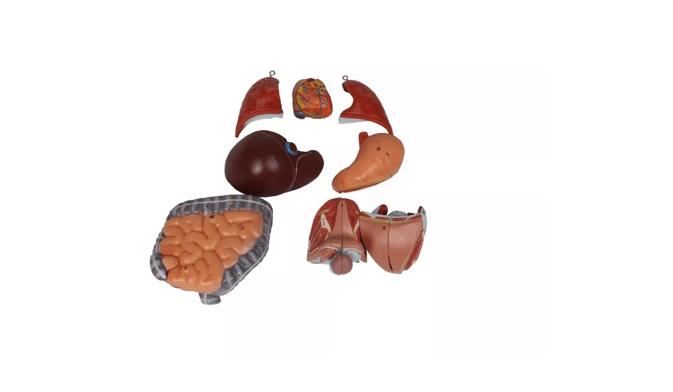

Modellteile im Überblick:

Grundkörper mit zwei Kopfhälften

Eine Kopfhälfte mit herausnehmbarem Gehirn

Zwei Lungenhälften

Herz (zweiteilig zerlegbar)

Magen

Leber

Darmpaket mit abnehmbarem Blinddarmdeckel

Weibliche Geschlechtsorgane (zweiteilig)

Männliche Geschlechtsorgane (zweiteilig)